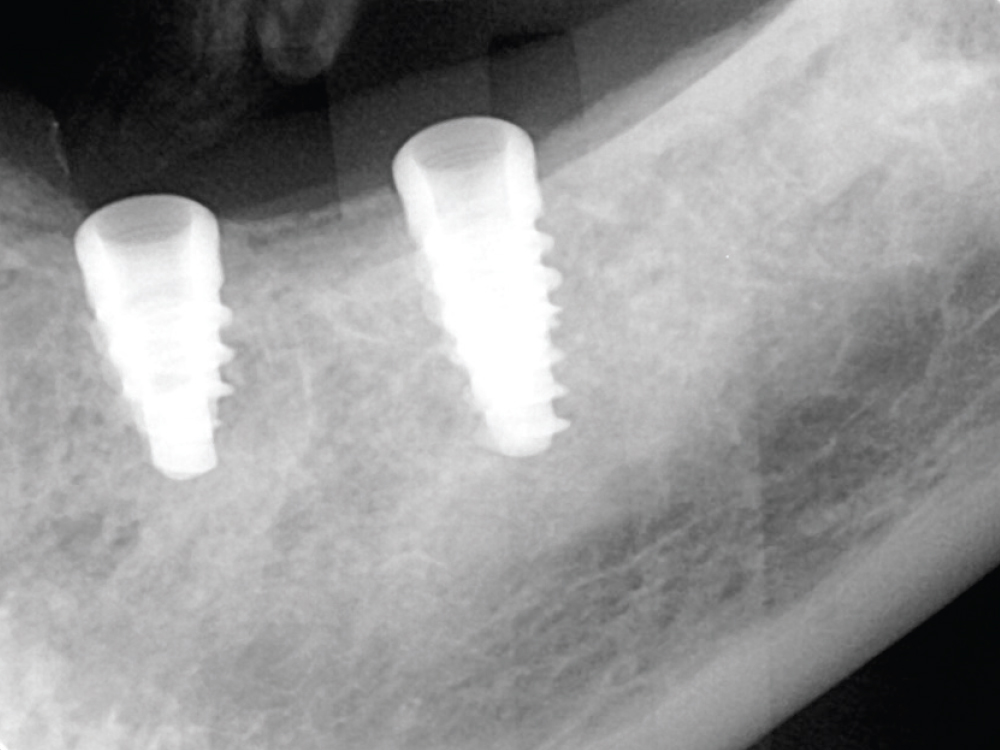

JN: Yes. I did it with the help of mentoring, and it’s certainly one of the more interesting cases I’ve done in my career. I placed seven implants in the maxillary arch. This was for a gentleman I edentulated a while back. He came in, only had a few teeth left and wanted a denture. His whole reason for holding on to those few remaining teeth was because it allowed him to play the trombone, which was his life’s passion. But his teeth had gotten to the point where they were getting loose due to periodontal disease and had decay. They had to come out.

I talked to him during his initial exam and said, “I really can’t promise that you’re going to be able to play the trombone with a denture.” I told him that implants were his best option and tried to convince him to have his teeth extracted and implants placed at the same time, but he decided he’d rather get a denture and see how things went.

I took his teeth out, I placed his denture, and it came true: He couldn’t play his trombone. He tried to make it work for several months, started getting depressed, and then came back to see me. By that time, I was starting to place implants and I presented the option to him. It was outside of his financial comfort zone for him to receive a fixed prosthesis, but I gave him a huge discount in order for me to offer that service in my practice. I gave him a number he couldn’t refuse. I felt this was beneficial to both of us — I was able to place his implants and he would be able to play his trombone again.

He agreed to be my first full-arch implant patient and the process actually went quite smoothly. I placed the implants through a surgical guide and restored the arch with a BruxZir Implant Prosthesis from Glidewell, which has a clinical workflow that is easy for anyone to follow and takes any kind of guesswork out of the process with step-by step instructions, checklists and video tutorials. Dentists who are both new to the process and seasoned veterans in prosthetics who have done full-arch cases before like I have will find that this is an accessible solution that streamlinlines the restorative workflow.

The patient is just ecstatic now that he’s got his old life back and is able to play his trombone. He’s promised to come back and play his trombone for me — just as a little celebration and to show his appreciation. To me being able to positively impact a patient’s life like this is what dentistry is about. This is a great example of how offering implants in the general practice helps patients who otherwise may never receive the treatment they need.

Dr. Nosti recently completed his first full-arch implant case, placing seven implants for a patient who was unhappy with a denture he had received several months prior, which made it nearly impossible to play his trombone. After placing the Hahn implants through a surgical guide and allowing the sites to heal, Dr. Nosti restored the implants with a BruxZir Implant Prosthesis, fully restoring function and allowing the patient to resume his life as a musician.